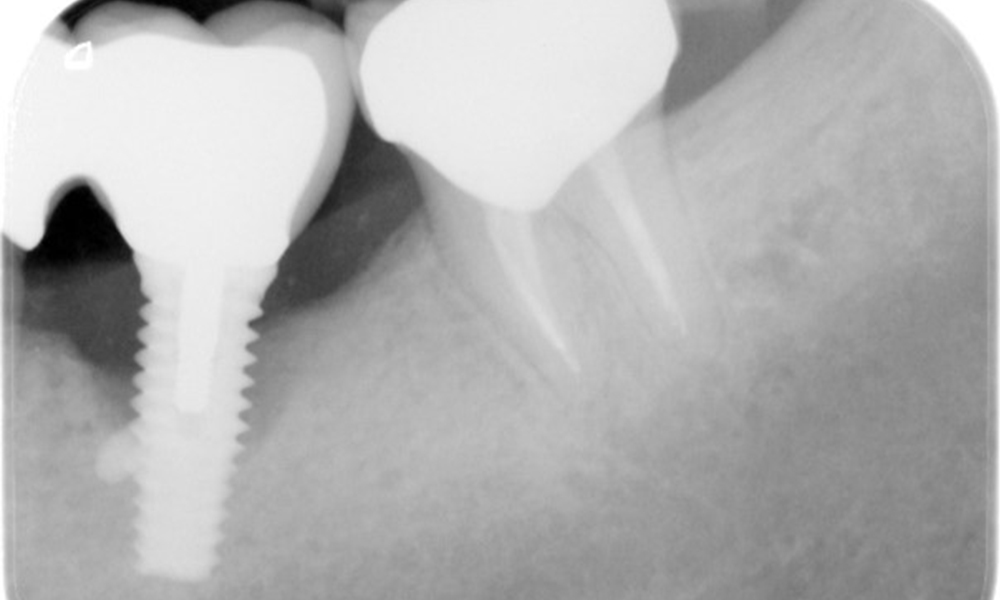

The X-ray images show the progression of bone loss.

The X-ray images show the progression of bone loss. OPG from 29.06.2020 (left) and OPG from 26.02.2024 (right).

The X-ray images show the progression of bone loss in the area of the implant in region 36: dental film from 11.02.2021 (left) and dental film from 18.01.2024 (right).